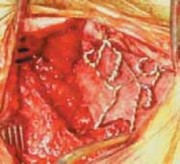

TECH FIG 1•

(continued)

C.

A Luque wire is passed through the occipital burr hole and another wire is passed sublaminarly under the arch of C2 or through the base of the C2 spinous process.

D.

Occipital wire is looped on itself.

E.

Schematic drawing showing occipital wire looped on itself and the wire passed through the base of the C2 spinous process.

F.

Graft (

arrow

) placed between the occiput and C2.

G.

The wires are tightened over the graft in a figure 8 shape, twisted, and cut. H. Schematic drawing showing the graft placement and securing with wires. #### OCCIPITOCERVICAL ARTHRODESIS WITH RIB GRAFT